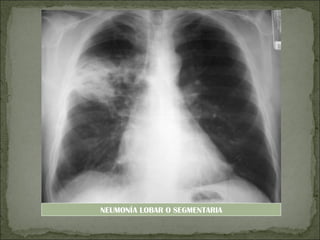

 Neumonía lobar o segmentaria: lesiones

inflamatorias de todo un lóbulo.

 Radiografía de tórax:

-Neumonía lobar o segmentaria: opacidades

homogéneas en un lóbulo o segmento

NEUMONÍA LOBAR O SEGMENTARIA